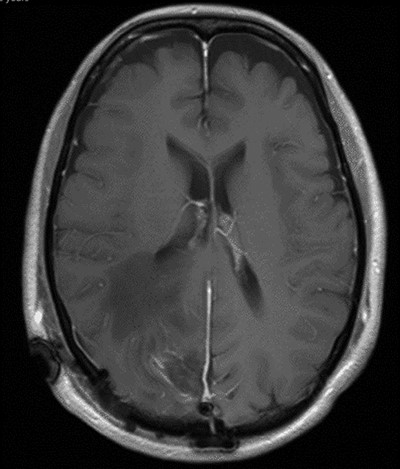

Two weeks later, whilst awaiting surgery, she attended the Emergency Department with a fever of 38.6°C and mildly raised inflammatory markers (WCC 10.4, Neut 8.4). Urine dip and CXR were unremarkable. The source of the infection was not isolated and the emergency medicine physicians discharged her with a course of empirical oral antibiotics. The neurosurgical team were not made aware of this attendance. Twelve days later, she underwent a planned neuronavigation-planning MRI scan as an outpatient. This was arranged one week prior to the scheduled surgery, in line with our departmental protocol. The MRI was reviewed and two new rim-enhancing collections superior and inferior to the tumour were noted, associated with extensive perilesional oedema (Fig. 2A and B). The patient was then immediately contacted via telephone and reported new worsening of headaches and new right sided weakness. She was admitted to hospital directly for assessment and emergency treatment. Her inflammatory markers on admission had risen to a WCC of 19.5, Neut 16.6, but CRP was <1. She was started on an emergency steroid treatment and subsequently underwent craniotomy, total resection of the meningioma and drainage of the intraparenchymal paratumoural abscesses. Intra-operatively the brain was swollen; pus collections were encountered in abscess cavities superior and inferior to the solid tumour, which had a necroticcore.

T1 weighted MRI postgadolinium enhancement in both sagittal (A) and coronal (B) views. There are two new rim-enhancing cystic lesions. A superior lesion of 31.4 mm as measured on the coronal reconstructed images and is abutting the adjacent dura of the right parietal lobe and is sited superior and lateral to the right occipital lesion. Another lesion sited inferior to the known right occipital lesion is the larger of the two lesions and has a septation within it. This measures approximately 34.4 mm on the coronal reconstructed images. On the sagittal images, it can be seen that the anterosuperior enhancing border of this lesion has a thicker and more ill-defined age. There is an adjacent vasogenic oedema.